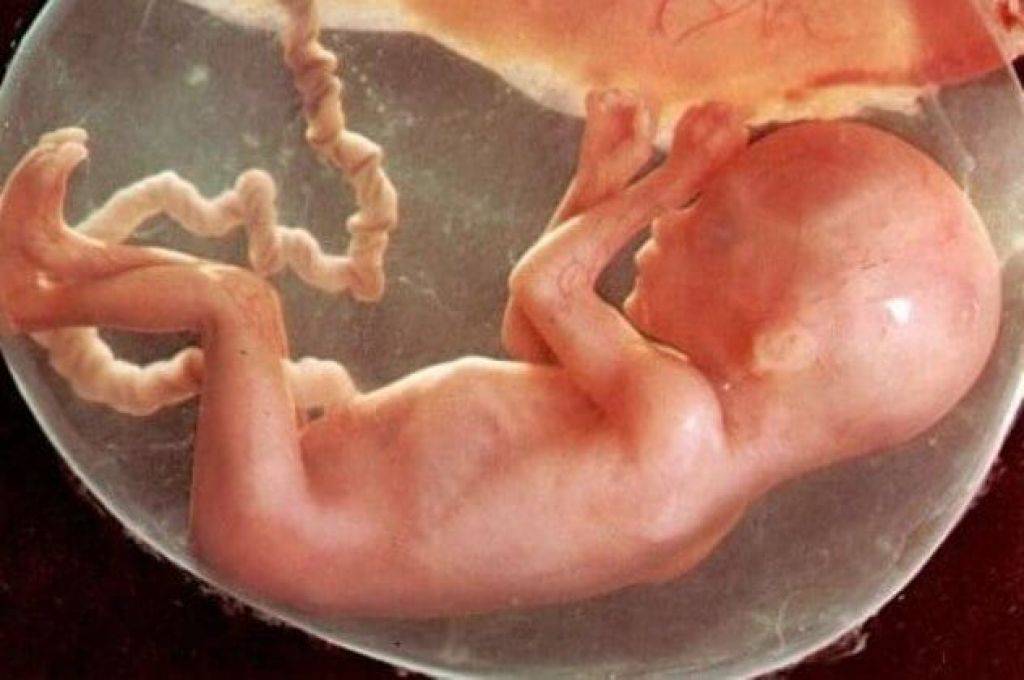

Важный этап: развитие малыша на 20-й неделе беременности

Раздел: Снимки-откровения